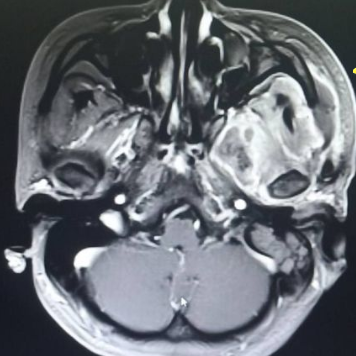

术前核磁

术前增强MRI